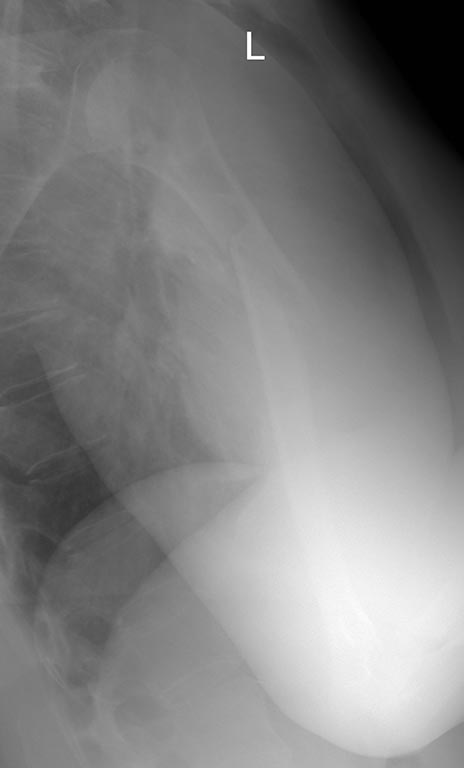

[Ortho] Нестабильность остеосинтеза, несращение перелома плечевой кости.

Еще Рентгенограммы

Имя     : 2.JPG